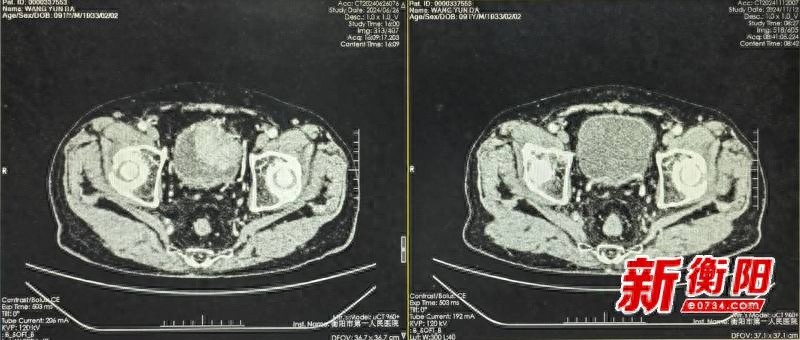

瑞金医院首位接受国产质子治疗的前列腺癌患者透露,当国产质子治疗系统招募志愿者参与临床试验时,他果断选择加入。治疗期间,患者未感受到痛苦,也未遭受创伤。医护人员展现了卓越的专业技能和周到细致的服务。经过三年半的定期检查,患者的健康状况保持稳定。他对我国科技进步取得的成就充满敬意,该技术让广大民众得以享受到高质量的医疗服务。